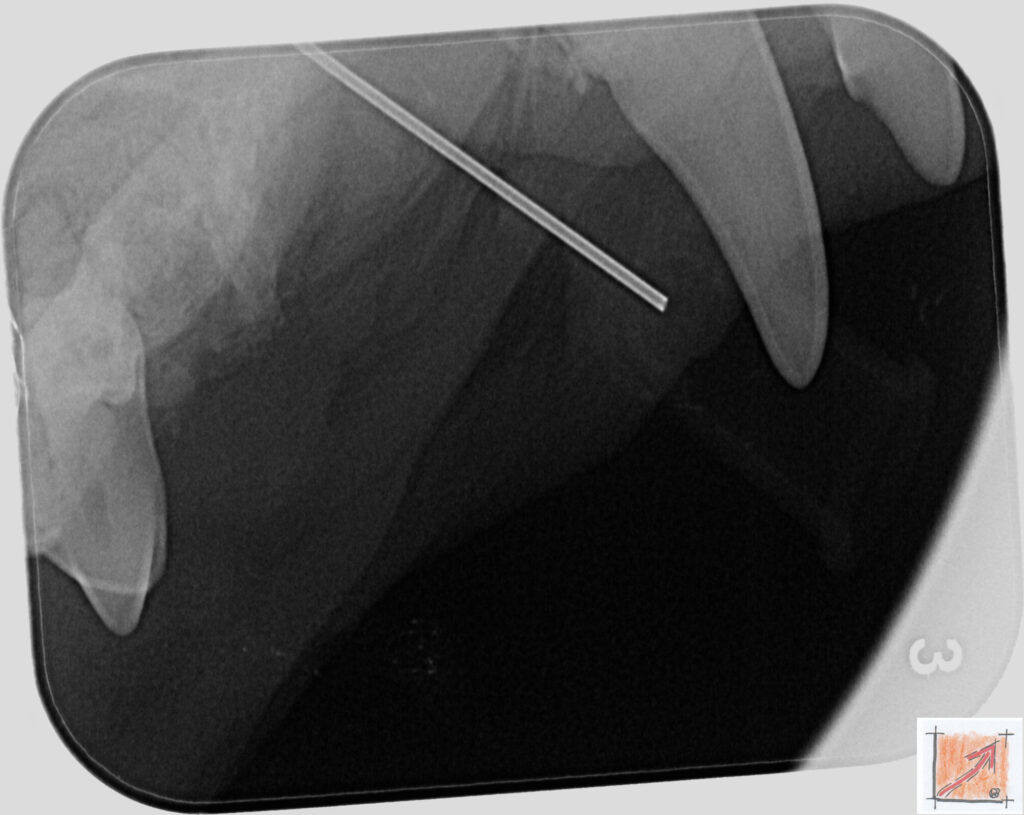

Röntgenbilder vom Thierrischen Orakel bei der Zahn-OP:

Warum Dentalröntgen beim Chihuahua lebenswichtig ist:

Ein Blick hinter die Kulissen von Chihuahua-Zähnen:

In dieser Galerie zeigen wir exklusive intraorale Röntgenaufnahmen einer Zahn-Operation beim Thierrischen Orakel als Chihuahua vom BauFachForum. Während oberflächlicher Zahnstein oft sichtbar ist, verbirgt sich die wahre Gefahr für das Herz meist unter dem Zahnfleischsaum.

Das digitale Dentalröntgen ist der Goldstandard in der modernen Tiermedizin, um parodontale Entzündungsherde und Wurzelabszesse sicher zu diagnostizieren. Für Chihuahuas wie dem Thierrischen Orakel, mit Mitralklappeninsuffizienz ist dieser diagnostische Schritt essenziell. Nur wenn versteckte Bakterienherde an der Zahnwurzel oder mit dem Fachbegriff Apikalabszesse erkannt und saniert werden, kann das Risiko einer bakteriellen Endokarditis oder einfach ausgedrückt einer Herzinnenhautentzündung minimiert werden.

Unsere Aufnahmen von Patienten dem Thierrischen Orakel verdeutlichen den Unterschied zwischen einer rein optischen Zahnreinigung und einer medizinisch fundierten Sanierung unter Röntgenkontrolle.

Chihuahua Mitralklappeninsuffizienz Trachealkollaps:

Wichtig ist im Vorfeld die Zahnhygiene des Chihuahuas. Die Bilder zeigen Dentale Röntgenbilder vom Thierrischen Orakel als Chihuahua-Hund während seiner Zahn-OP. Darstellung von Kieferknochen und Zahnwurzeln zur Diagnose von Parodontitis.

Zahnröntgenaufnahme bei Chihuahua Thierry:

Untersuchung der Zahnwurzeln auf Entzündungsherde als Prophylaxe gegen bakterielle Endokarditis.

Intraorales Dentalröntgen eines Chihuahuas:

Die Bilder zeigen Zähne und Wurzelstrukturen im Unterkiefer zur Planung einer Extraktion bei hochgradigem Zahnstein.